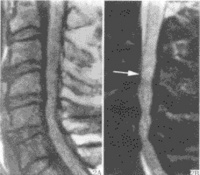

三MRI表现

1.多发在长管骨的干骺端,病灶呈圆形或椭圆形,其长轴与长骨纵轴一致。

2.病灶于T1WI上多呈低或中等均匀信号,T2WI呈明显均匀高信号,若囊液内有出血或含胶样物质则T1WI和T2WI上均呈高信号,少数呈多房改变时T2WI上可见低信号纤维间隔。

3.病灶周边骨壳呈圆圈样低信号,一般完整,边缘清晰。局部骨皮质变薄,无骨膜反应。常伴发病理性骨折,表现为骨皮质断裂,骨片陷落而插入病灶内,称之为骨片陷落征(fallenfragmentsign),此征在T2WI上显示较清晰即在高信号的囊液中见低信号的骨片线条影。

4.增强扫描:病灶不强化。